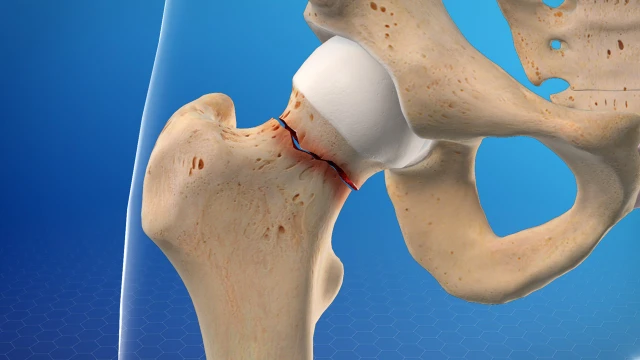

:format(webp)/gay_co_xuong_dui_1_3bdc6dc8b1.jpg)

Gãy cổ xương đùi là một tình trạng cấp cứu y tế nghiêm trọng, có thể gây ảnh hưởng lớn đến cuộc sống, đặc biệt ở người trên 65 tuổi. Đây là chấn thương phổ biến, nhưng hầu hết các trường hợp đều cần phẫu thuật để cố định xương gãy, thậm chí có thể phải thay khớp háng. Quá trình hồi phục sau phẫu thuật thường kéo dài vài tháng.